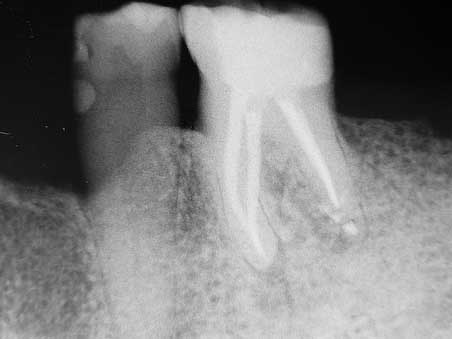

Apikale Aufhellung 001 Bild 6

Veröffentlicht 10. Februar 2009 am 452 × 339 in Apikale Aufhellung (1)